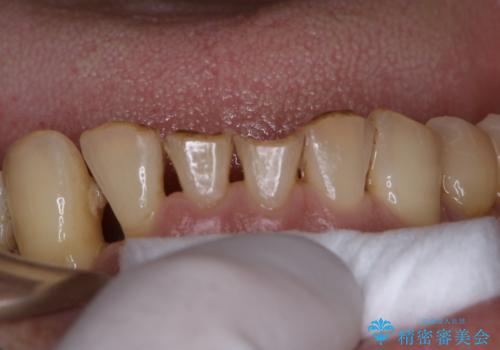

- 治療中のメンテナンス希望の方です。PMTC30分コースを行いました。

口の中には、目には見えない細菌がたくさんいます。歯周病は細菌による感染症です。歯面のプラークや着色(ステイン)など、細菌をしっかり除去し、治療の妨げにならないよう、治療中にPMTCを行うことも大切です。